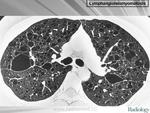

лимфангиолейомиоматоз

Типичный пример патологии при которой основным патерном являются кисты - :

Лимфангиомиоматоз.

Из архива AFIP. Лимфангиолейомиоматоз.

Лимфангиолейомиоматоз.